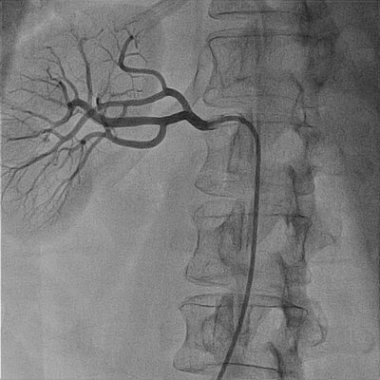

Renal Angiography / Angioplasty

Renal angiography or Renal Angioplasty refers to the procedure carried…